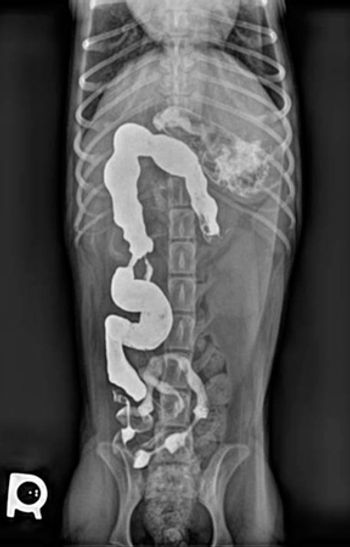

Add a little contrast to help you find your diagnosis.

Our newest expert Dr. Tasha Axam delivers her thoughts on esophageal imaging.